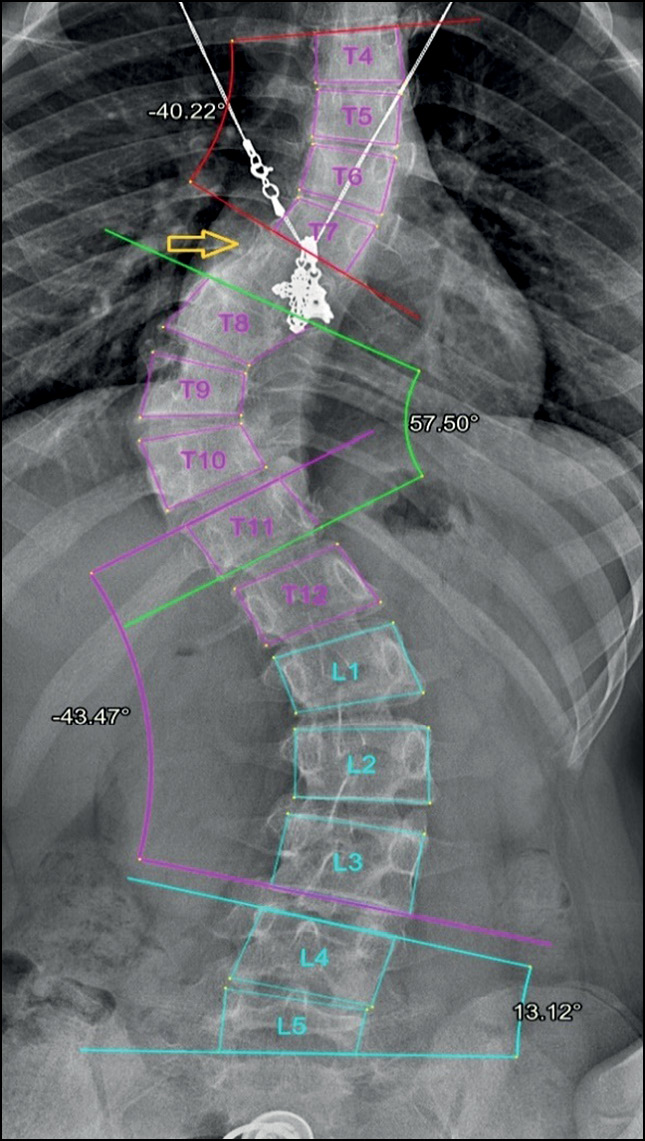

In addition, in most cases, the system accurately evaluated radiographs with severe scoliosis (grades III and IV), although errors in vertebral detection and numbering or errors in measuring Cobb’s angle sometimes were noted. Grade IV scoliosis is characterized by maximum vertebral rotation, with displacement of the pedicle beyond the midline and deformation of the vertebral body. Thus, the usual shape of the vertebra changes, and the edges of its body become less defined (Fig. 9).

Fig. 9. Specifications of vertebral marking in radiographs with grade 3 and 4 scoliosis. Errors in detection and numbering of vertebrae caused by the unusual shape of the vertebrae (yellow arrow).